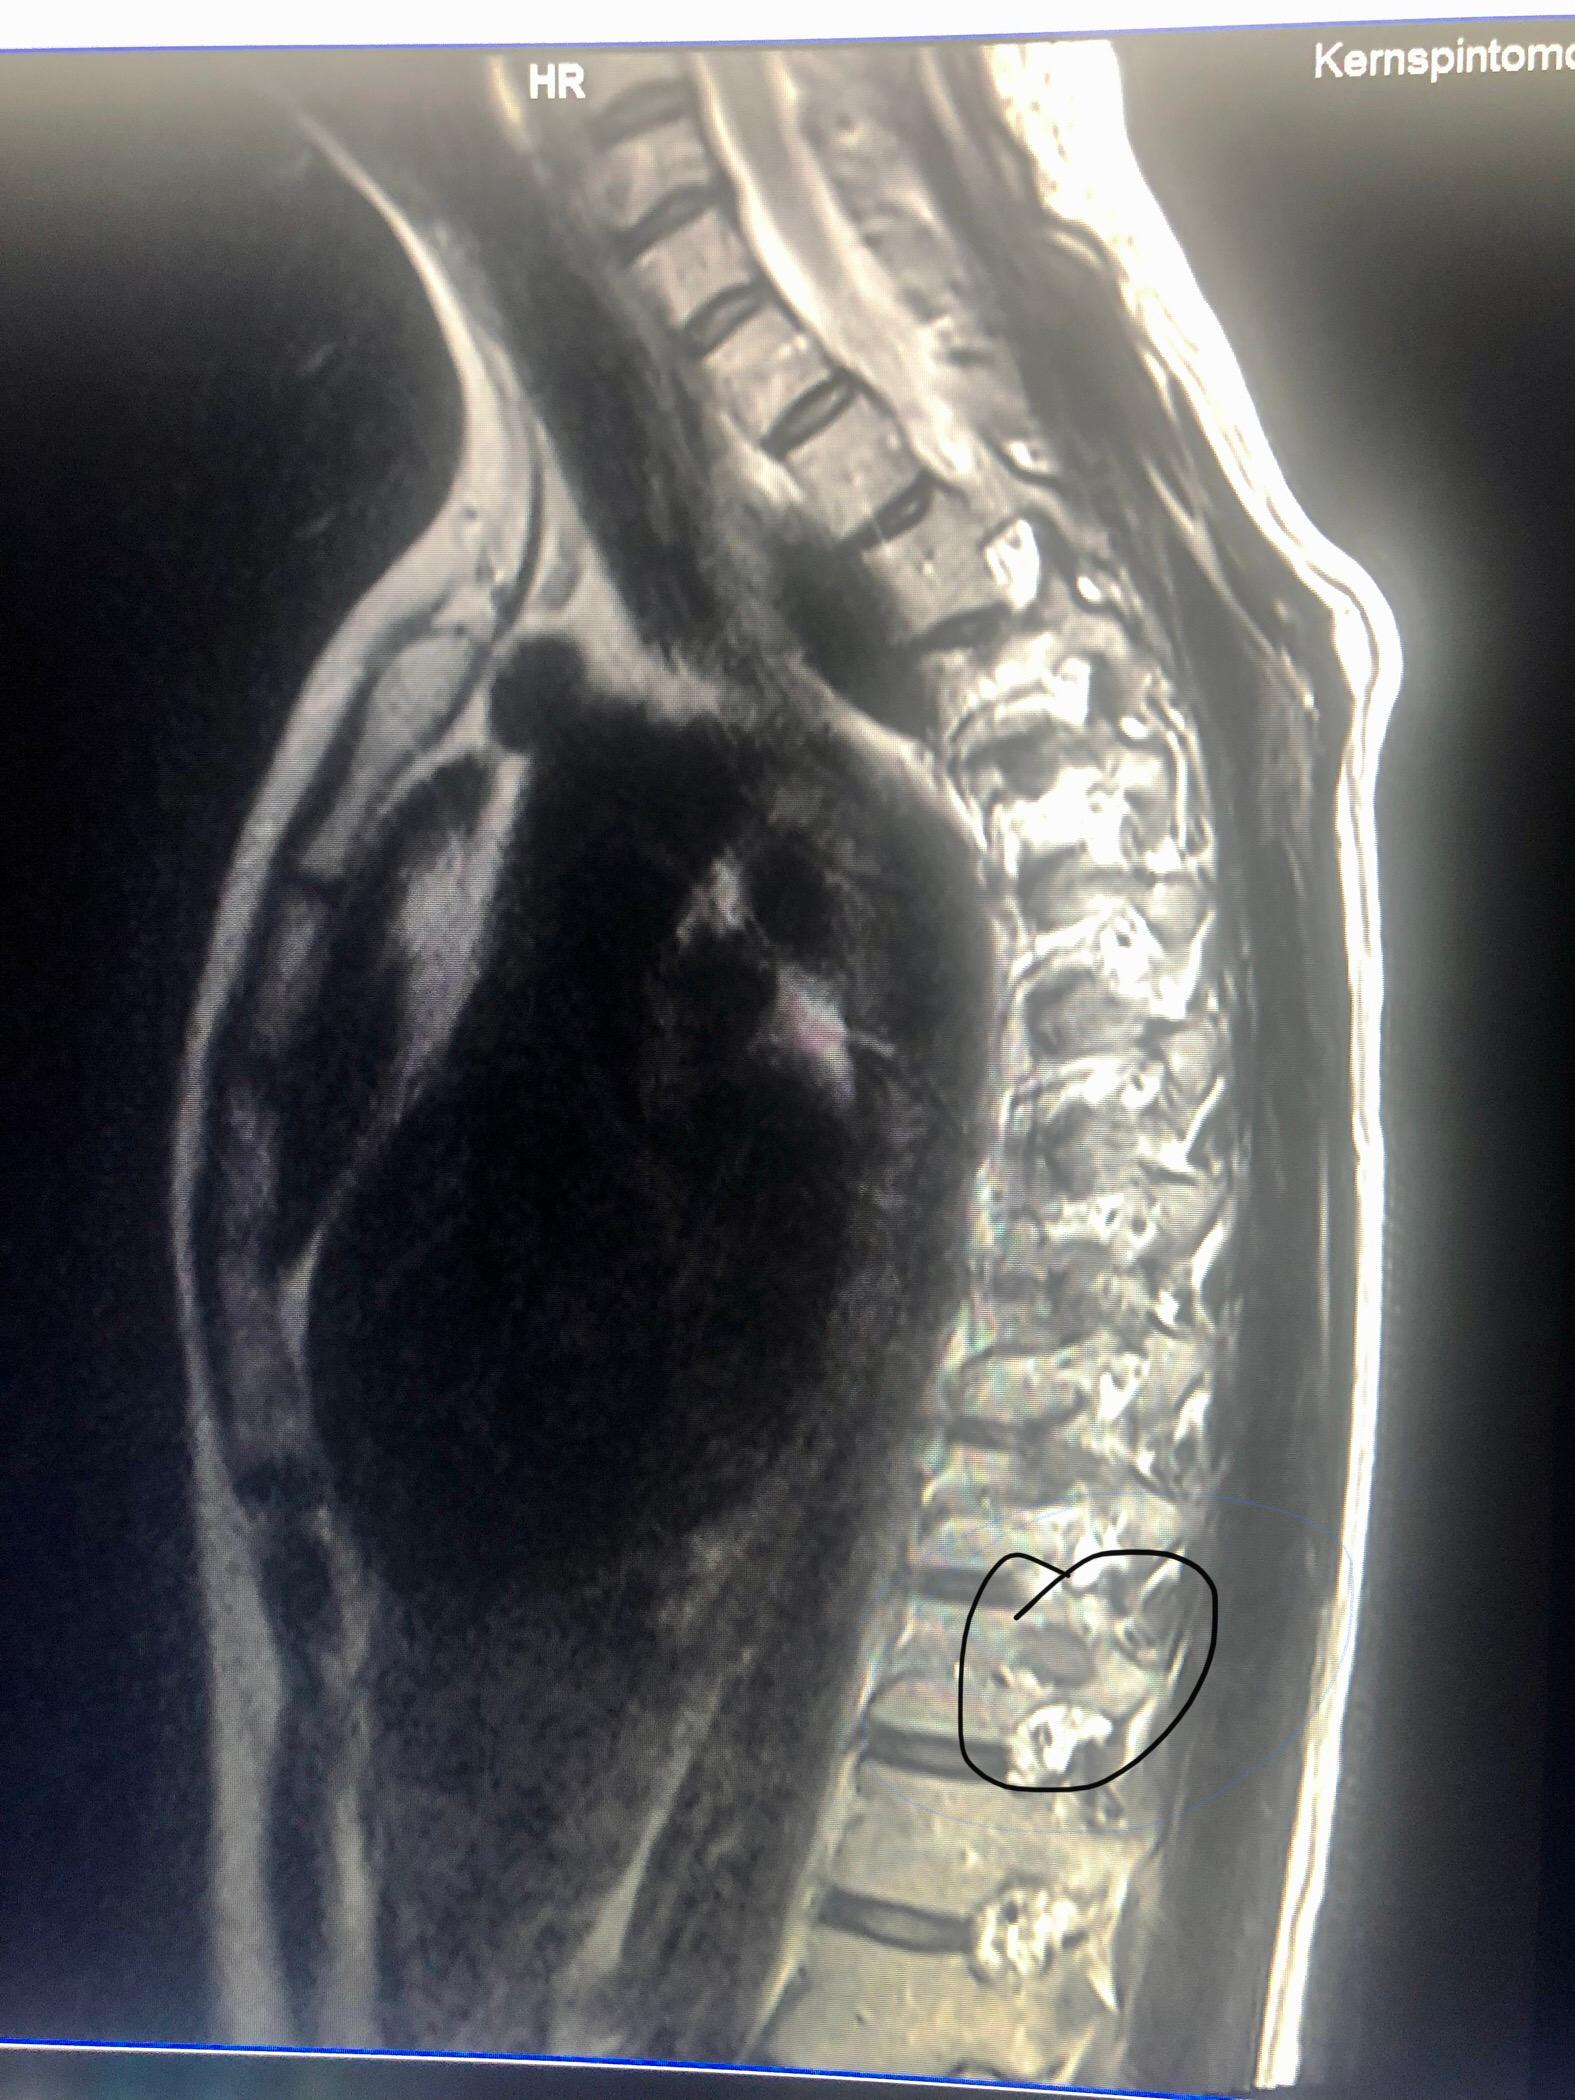

MRT bei einem Bandscheibenvorfall der BWS Bei einem Bandscheibenvorfall der Brustwirbelsäule eignet sich ein MRT besonders gut um festzustellen auf welcher Höhe der Bandscheibenvorfall genau stattgefunden hat und wie weit die Bandscheibe von ihrer natürlichen Position abgewichen ist.

Was passiert bei einer MRT-Untersuchung. Wegen eines vermuteten Vorfalls sehen werden die Schulterblätter nicht drauf sein. Im Normalfall übernehmen private Krankenkassen die vollen Kosten. Sie zählt wie Röntgen Ultraschall und CT zu den bildgebenden. Vor allem bei Verdacht auf einen Bandscheibenvorfall der Lendenwirbelsäule wird ein MRT durchgeführt. Sie waren auch normal angeordnet. Dann sieht man nur den reinen Wirbelsäulenbereich mit den Wirbelkörpern Wirbelkanal Bandscheiben etc. Das kommt darauf an wie das MRT eingestellt ist. Bei der MRT können das Herz das Gehirn Nervengewebe Muskelgewebe Blutgefäße und generell Weichteilgewebe untersucht.

Aber auch Bandscheiben Gelenke Muskeln oder Blutgefäße können mit dem Verfahren untersucht werden. Habe starke brennende Schmerzen im re Oberschenkel hinten und seitlich außen. Die fühlt jemand der begnadet ist d. Die Darstellung in der MRT ist aufgrund des deutlich besseren Weichteilkontrastes der CT-Untersuchung überlegen eine Diagnostik dieser Fragestellungen ist aber auch in der CT möglich. Fühlt sich wie eine Entzündung und Verhärtung an. Was sieht man beim MRT. Die Brustwirbelkörper sehen unter den Gesichtspunkten Form Größe und Anzahl normal aus.